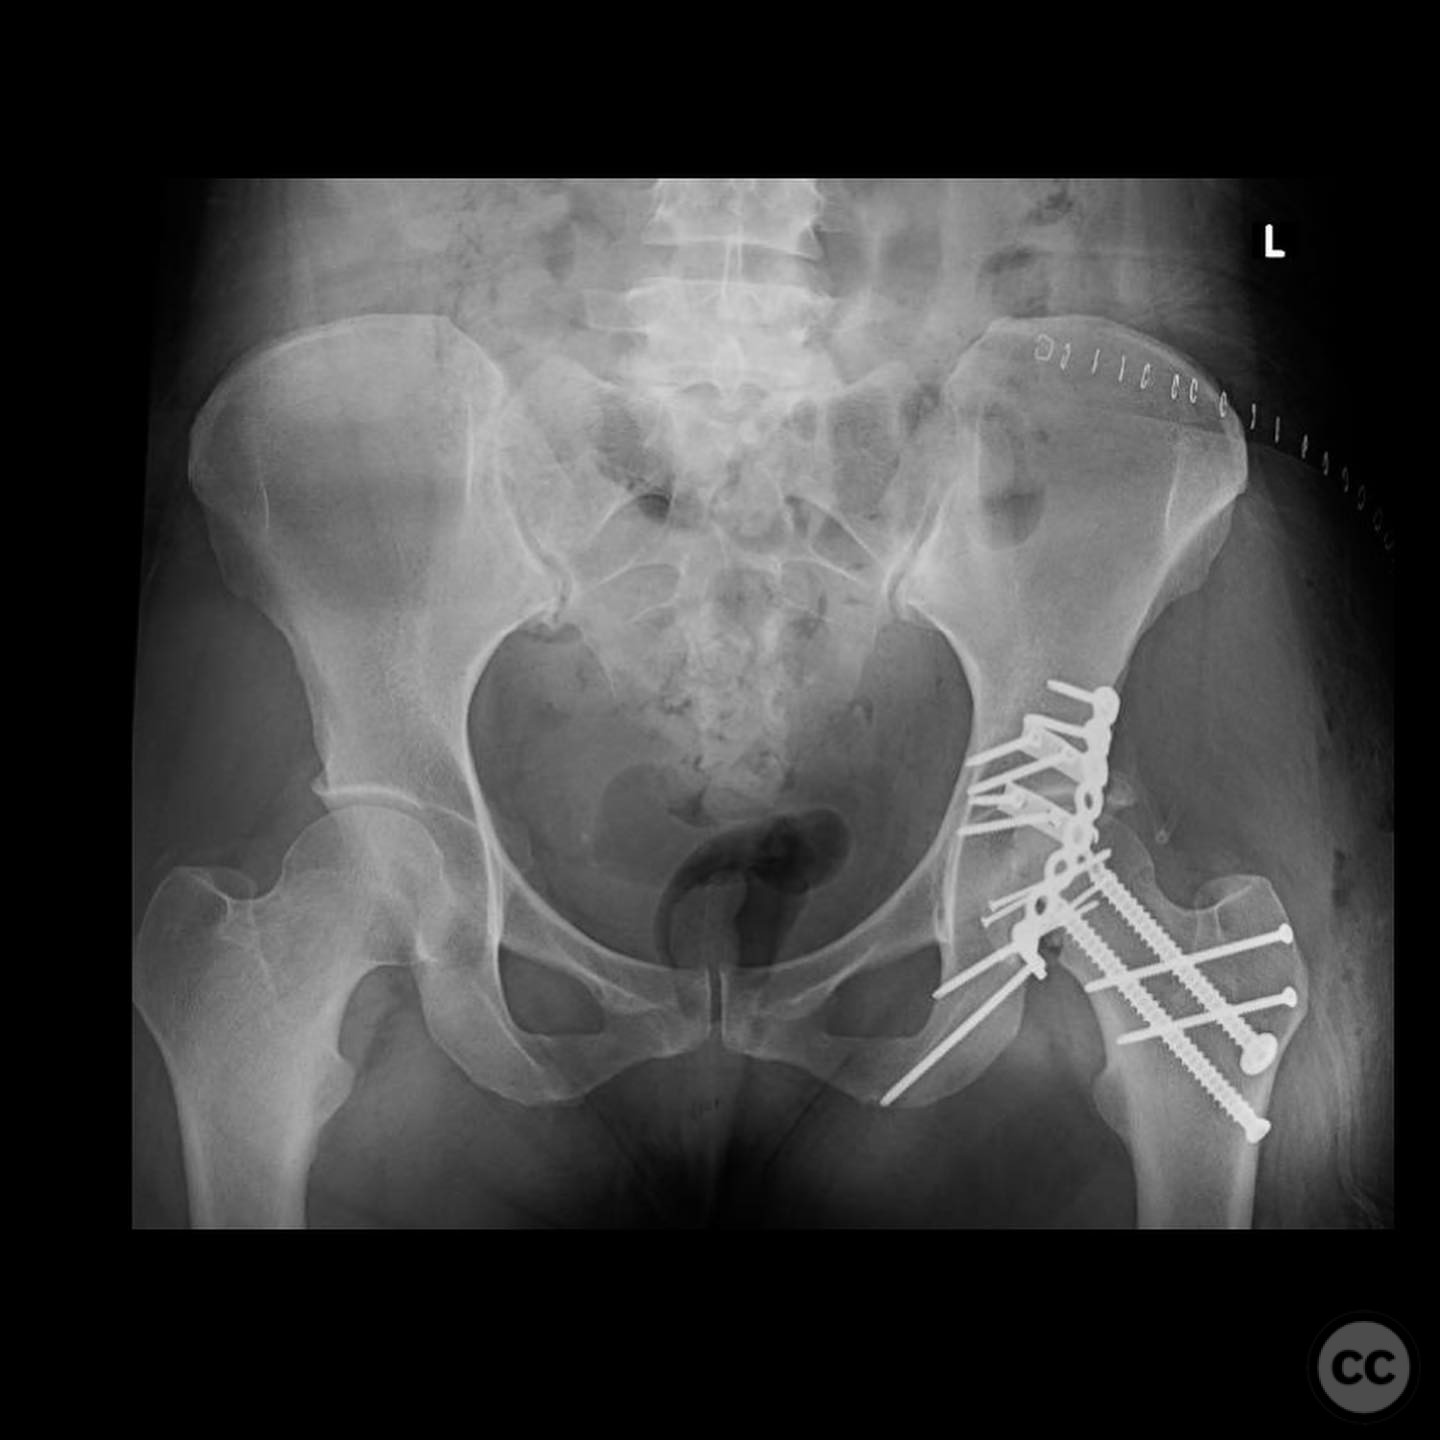

Anatomical surgical approach:  A Gibson approach was utilized, involving a trigastric slide osteotomy to achieve anterior dislocation of the hip. This allowed access to the femoral head for reconstruction using an allograft. The posterior wall was accessed for capsulolabral repair.

The femoral head defect required meticulous reconstruction using a femoral head allograft to restore its round shape. The posterior wall instability was addressed with spring plates and three suture anchors to reattach the capsulolabral complex. The reconstruction aimed to achieve a stable and congruent hip joint.

Orthopaedic implants used:   Femoral head allograft, spring plates, suture anchors.